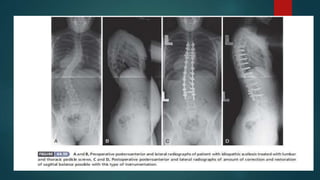

ADOLESCENT IDIOPATHIC SCOLIOSIS

 Adolescent idiopathic scoliosis is present when the spinal deformity is recognized

after the child is 10 years of age but before skeletal maturity.

 This is the most common type of idiopathic scoliosis.

 The characteristics of adolescent idiopathic scoliosis include a three-dimensional

deformity of the spine with lateral curvature plus rotation of the vertebral bodies.

 Most idiopathic curves are lordotic or hypokyphotic in the thoracic region.